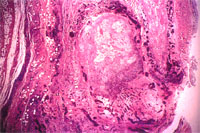

組織病變: 肺臟可見間質細胞明顯增生,間質部並可見粉紅色均質樣物之沉積,少量融合細胞(圖3),支氣管周圍則有淋巴球浸潤長淋巴小結增生,血管周圍有少量粉紅色物質沉澱。肝臟可見肝小葉間有粉紅色物質沉澱。脾臟馬氏小體周圍有大量粉紅色物質沉澱。關節滑膜結締組織增生,新血管生成,並有大量嗜中性球及單核球浸潤(圖2)。以剛果紅染色,上述肺、及脾之血管周圍有粉紅色物質,經剛果紅染色及偏光鏡檢查,判定為Amyloid物質(圖4)。